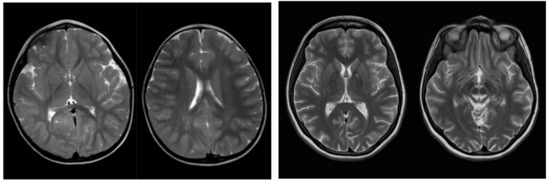

2.1.2. Technical Investigations